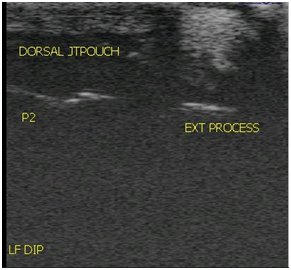

Digital Ultrasound

A high quality ultrasound is a very valuable imaging tool for evaluating and diagnosing a wide range of conditions primarily but not limited to soft tissue. Musculoskeletal structures such as tendons, ligaments, joints, muscles and bone surfaces may be evaluated for signs of injury or infection. Once an injury is found, ultrasound allows for monitoring healing progress. It can be used for ultrasound guided injections of structures such as the sacroiliac and cervical joints. Ultrasound can aid in diagnosing the cause of colic and other abdominal conditions as well as conditions of the thorax such as pleuropneumonia and lung abscesses. Another very common use of ultrasonography is to monitor reproductive cycles and pregnancy in the broodmare.